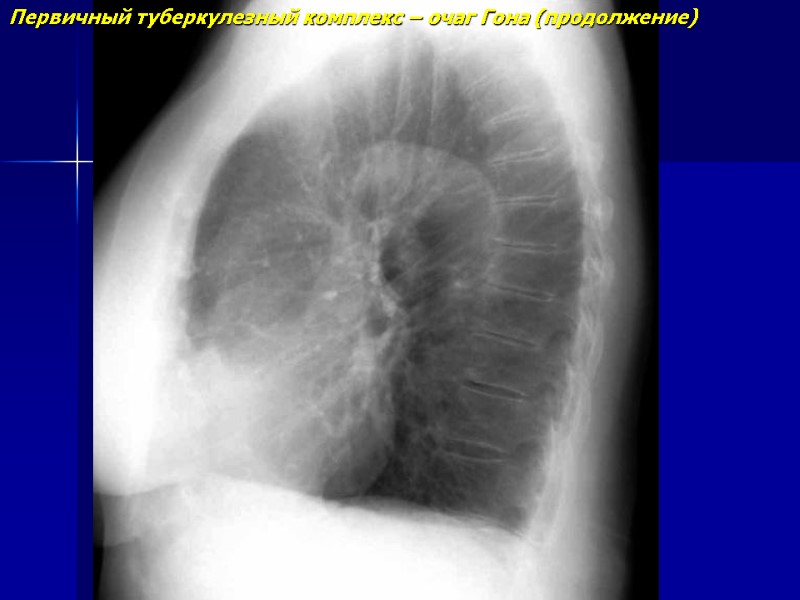

Первичный туберкулезный комплекс – очаг Гона (продолжение)